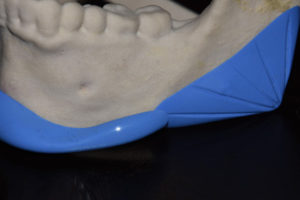

Chin and Jaw Angle Implant Overlap in Total Jaw Augmentation Dr Barry Eppley Indianapolis